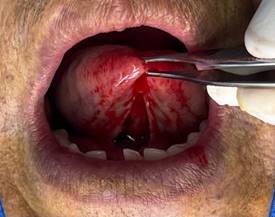

· Diéresis: Se sujetó la lengua con la ayuda de una pinza Adson con dientes, después se utilizó el electrobisturí realizando cortes lineales verticales o ligeramente convergentes hacia apical. (Figura 4)

Figura 4. Diéresis.

Elaboración: Los autores.

· Desprendimiento nítido del frenillo: Al terminar la primera fase de la diéresis se debe observar el desprendimiento nítido de la inserción del frenillo. Con este desprendimiento se intenta evitar la recidiva. (Figura 5)

Figura 5. Desprendimiento nítido del frenillo.